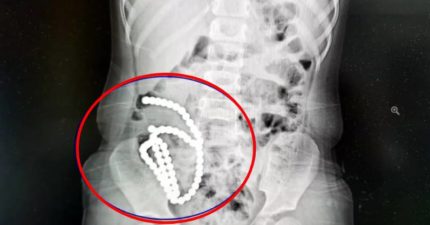

4歲妹照X光驚見「肚子整串白珠珠」 媽證實哥哥在玩!醫嘆:一輩子毀了

August 1, 2025

世界